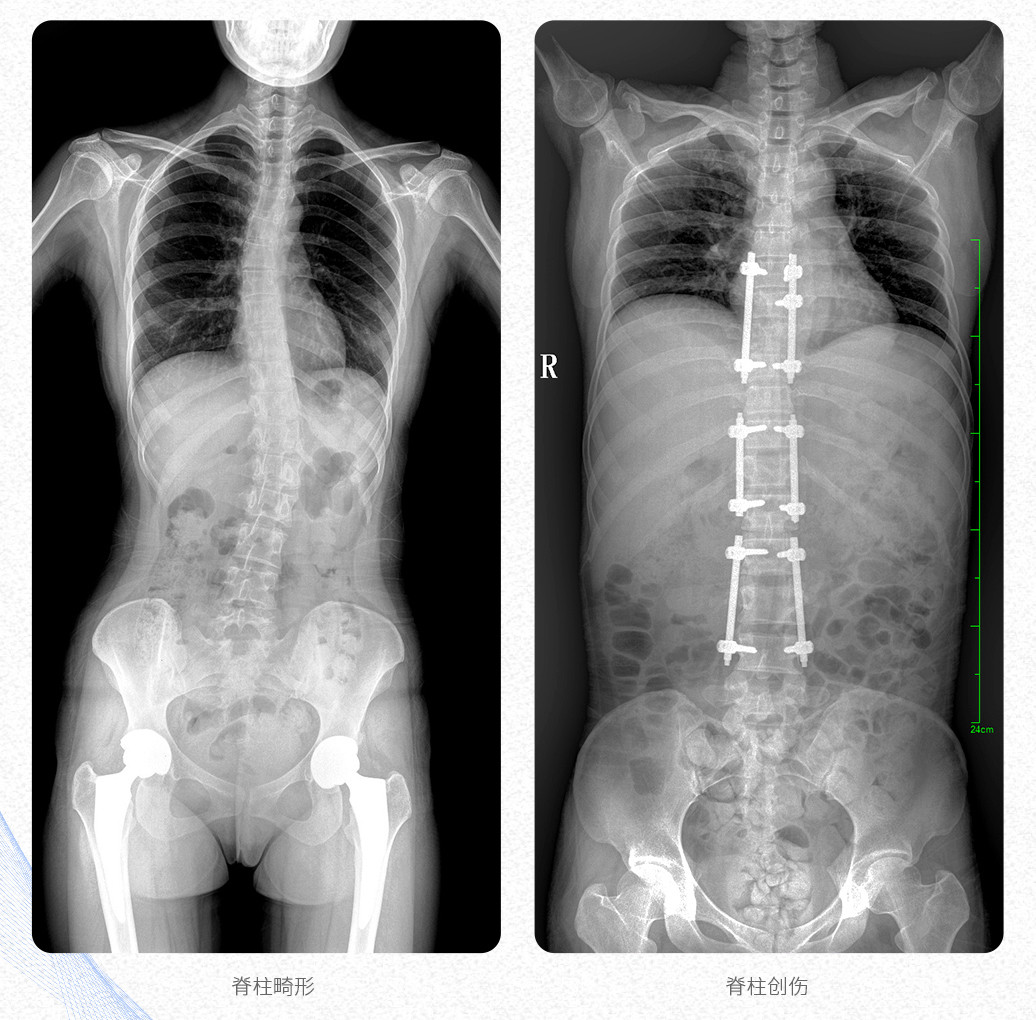

新品PLX8600大視野平板動態(tài)DR產(chǎn)品說明:

? ? 普愛醫(yī)療新推出自主研發(fā)的大視野平板動態(tài)DR——PLX8600,專為臨床大視野需求打造,圖像不拼接,可有效簡化影像科室檢查流程,提升工作效率,提高診斷精度,降低臨床拍攝劑量。